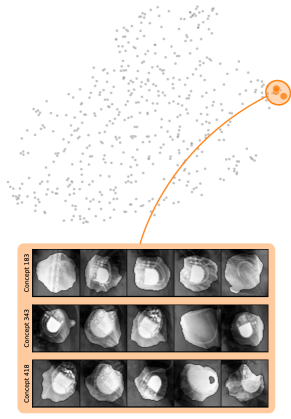

In contrast to detecting spurious samples, recent work focuses on identifying spurious model internals directly. This aligns with mechanistic interpretability, which seeks to decipher the internal mechanics of DNNs [56, 31, 13]. As outlined in Sec. 3.1, various global XAIs methods aim to explain the role of individual neurons, and these insights can be leveraged to detect spurious model internals by clustering learned concepts and identifying outliers. Given input data with samples, Pahde et al. [59] compute spatially aggregated relevances . Subsequently, they compute the pairwise cosine distance per column (i.e., channel/concept) and embed the resulting distance matrix in a low-dimensional space using dimension reduction techniques like t-Distributed Stochastic Neighbor Embedding (t-SNE) [71] or Uniform Manifold Approximation and Projection (UMAP) [49]. This low-dimensional embedding can be visualized to identify outliers through human inspection or anomaly detection algorithms, such as the Local Outlier Factor [12]. In summary, outlier representations can be identified in an embedding representation , obtained as

where reduces the dimension to , and the pairwise distance function is applied along all channel dimensions in the latent representation , either given by activations or relevance scores for layer . Note that this approach assumes over-parameterization resulting in redundant neurons, allowing to distinguish between similar and dissimilar concept representations. An example is shown in Fig. 4 (bottom), where latent relevance scores from a ResNet50 model trained for melanoma detection are used to identify outlier concepts, specifically a cluster focusing on band-aids rather than clinically relevant features. Notably, Eq. 3 can easily be extended to find outlier directions instead of neurons. Specifically, this involves a linear transformation of latent representations using the directions of interest, e.g., obtained in unsupervised manner as described in Sec. 3.1.

Next, we apply bias identification approaches from the model perspective by identifying outlier neurons based on activation pattern via DORA and relevance pattern by clustering pair-wise cosine distances between concept relevance scores. We focus on latent activations and relevances after the third residual block. DORA uses a distance function based on how neurons activate upon each others n-AMS, achieving high similarity when neurons activate upon similar input signal. A 2D visualization of the resulting distance matrix is shown in Fig. 6 (bottom left). Identified outlier concepts include ruler () and (white) hair (). We further compute pairwise cosine distances between latent relevance scores , aggregated over spatial dimensions, and apply UMAP to embed the resulting distance matrix in . This results in high similarity between neurons (concepts) that the model uses similarly for predictions. The concept clustering is visualized in Fig. 6 (bottom right), highlighting two outlier clusters focused on rulers () and blueish tint ().